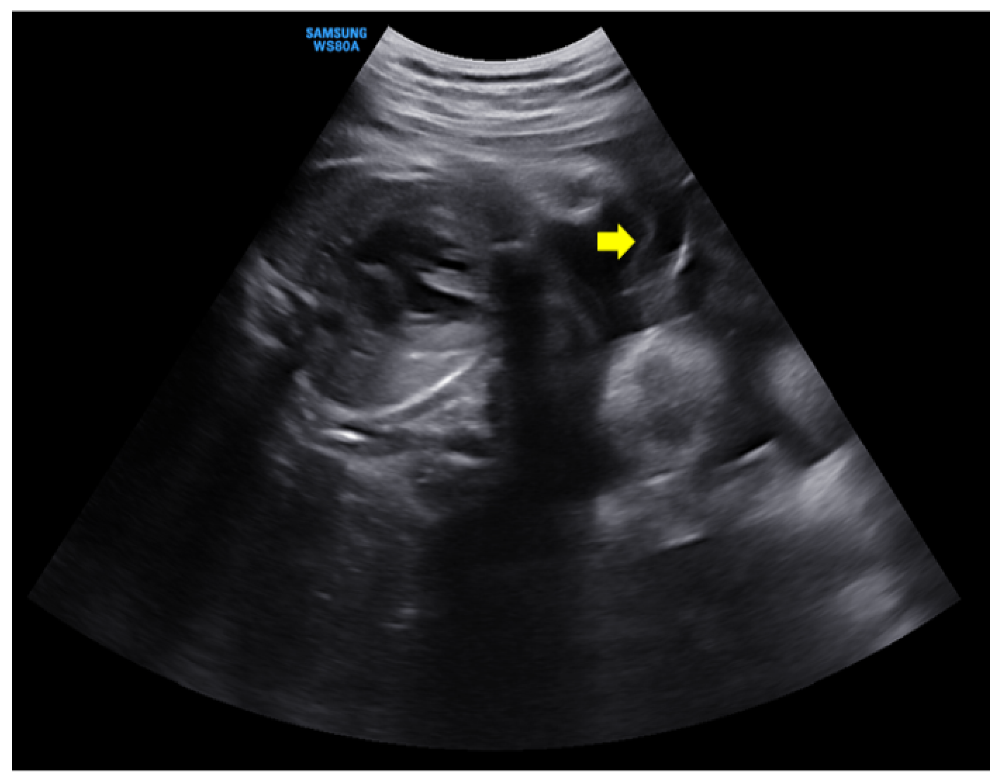

Figure 1. An ultrasonographic examination at 6 days before visiting emergency room. The intertwine membrane (yellow arrow) was well seen, and the amniotic fluid of both fetuses was normal.

A 28-year-old pregnant woman (gravida 1, para 0), who had attended regular prenatal checkups at our hospital outpatient clinic, visited our emergency room at 35 + 1 weeks of gestation because of persistent uterine contractions for 3 h. She felt fetal movements relatively distinctly and experienced no other obstetric problems such as vaginal bleeding or a vaginal watery discharge. She reported that she had felt her abdomen suddenly enlarge two days before, and that from then on, her dyspnea seemed to worsen. Her medical history was unremarkable, and her pregnancy had involved a spontaneous monochorionic diamniotic twin gestation. Amniocentesis had been performed because of the high risk of Down syndrome in the integrated test, but the patient had been diagnosed with a normal karyotype, and there were no structural abnormalities on detailed ultrasonography at 20 weeks of gestation. Ultrasonographic findings showed no marked differences in weight between the two fetuses and no significant differences in the amniotic fluid volume; therefore, the possibility of chronic TTTS was considered low. However, a short cervix was confirmed and a progesterone vaginal tablet was used. Growth delays were observed in both fetuses from 29 weeks of gestation, but there were no specific findings in infectious serum markers for congenital infections, and no significant problems in the umbilical artery, middle cerebral artery doppler, and amniotic fluid volume were observed. Serial ultrasonography was consequently performed every week. And, an ultrasound examination performed at an outpatient clinic 6 days before visiting the hospital showed an intertwin membrane, and the amniotic fluid volume were normal in both fetuses (Figure 1).